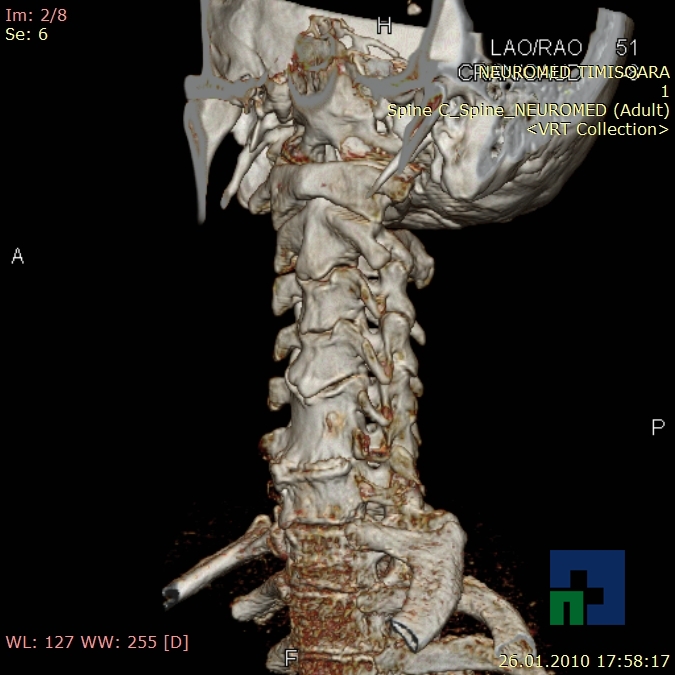

- Diagnosticul traumatismelor de bază de craniu

- Diagnosticul fracturilor:

- Cu înfundare

- Complexe cranio-sinusale

- Complexe cranio-etmoidale

- Complexe cranio-orbitare

- Complexe cranio-faciale